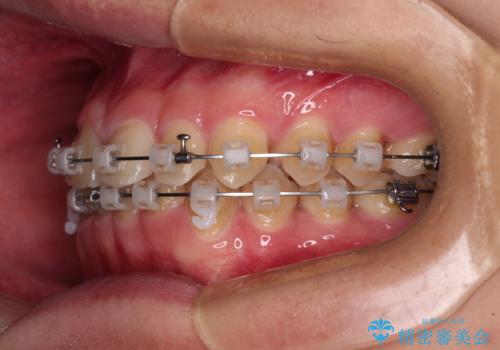

隙間とデコボコを治したい ワイヤー装置による矯正治療

- 矯正装置

- クリアブラケット

- 前歯のデコボコと隙間を気にして来院された患者様です。

治療手段としてはワイヤー装置でもインビザラインでも可能でしたが、インビザラインの自己管理は自信がないとのことで、ワイヤー矯正により隙間を閉じていくこととしました。

隙間の原因は舌の突出癖であったので、舌癖改善のためのトレーニングを指導しながら治療を進めて行くこととしました。

舌の突出癖がなかなか改善されず、治療開始時よりも隙間が大きく開いてしまう時期がありましたが、最終的にしっかりと閉じて終了することができました。